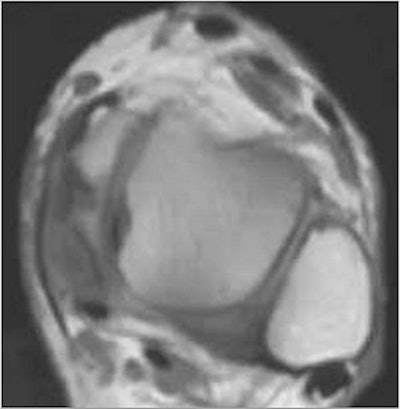

| In this case, ultrasound studies led to a diagnosis of PTT tendinosis with a partial tear (top and bottom), while T1-weighted MR image (center) indicated a complete tear. The patient was treated for a partial tear, however, as the orthopedic surgeon's evaluation of the PTT was more consistent with the ultrasound findings. Images courtesy of Dr. Krishna Nallamshetty. |

None of the discordant readings affected patient management because the clinical symptoms were more consistent with the ultrasound diagnosis, Nallamshetty said. Limitations of the study included a small sample size, an imperfect gold standard, and lack of surgical correlation, he said.